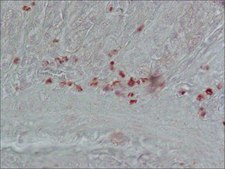

competitive inhibition ELISA: 1:1000-1:2000, immunohistochemistry (formalin-fixed, paraffin-embedded sections): 1:8,000 using indirect immunoperoxidase staining of human stomach

胆囊收缩素(CCK)属于胃肠激素家族,是一种神经肽激素和神经递质,通常存在于胃肠道(GI)和中枢神经系统(CNS)中。CCK功能包括胰腺酶分泌、胆囊收缩、肠蠕动; CCK也将抑制胃泌素诱导的酸分泌 该产品还可用于研究中枢神经系统和消化系统神经内分泌细胞中CCK的作用方式、组织差异表达以及细胞内和亚细胞定位。本品(CCK-8抗体)与硫酸化CCK-8特异性反应,与未硫酸化CCK-8和大胃泌素I具有交叉反应性。

胆囊收缩素(26-33)(CCK-8)抗体可用于免疫细胞化学法检测胰腺癌细胞中的CCK肽。也可用于酶联免疫吸附检测(ELISA)。